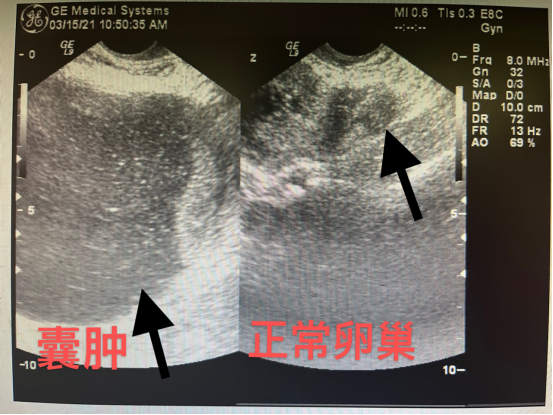

该患者72岁,半年前出现下腹间断疼痛,检查发现患者盆腔占位。张广美经检查确定肿物为囊性、直径12cm,来源于右侧卵巢,性质待定,需手术治疗。